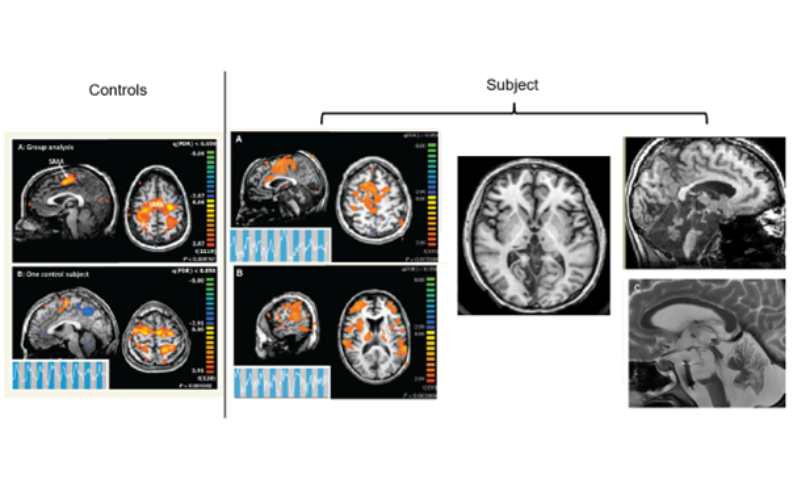

PDF) ADVANCES IN COGNITIVE NEURODYNAMICS (VI): Proceedings。11163.jpg。Gamma Oscillations in the Hyperkinetic State Detected with。

New Study Highlights Understanding of Brain Activity in

New Study Highlights Understanding of Brain Activity in